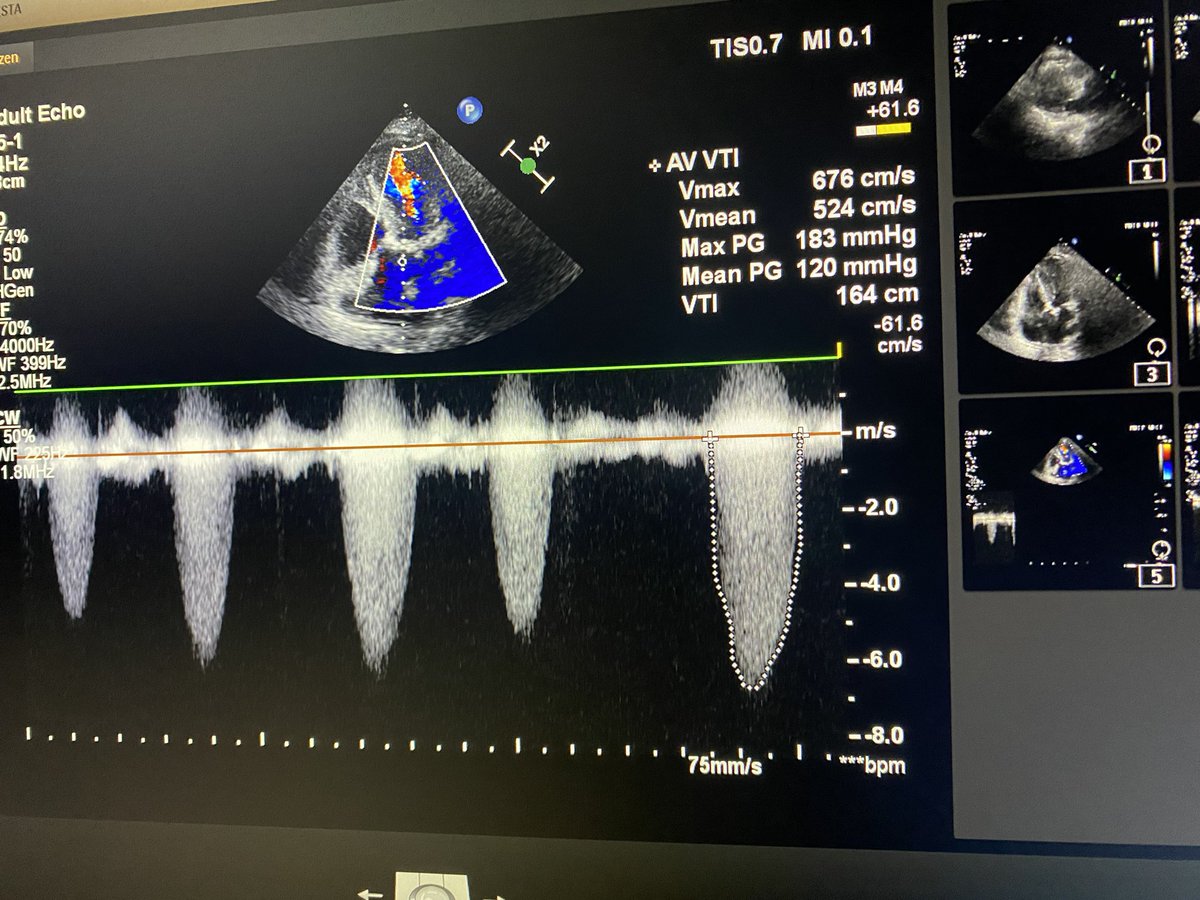

Consultant Cardiologist @EvercarePK 🫀 #echocardiography #noninavsive SRCardiology @farooqhospital @doctorshospital @EvercarePK #echofirst #cardiotwitter